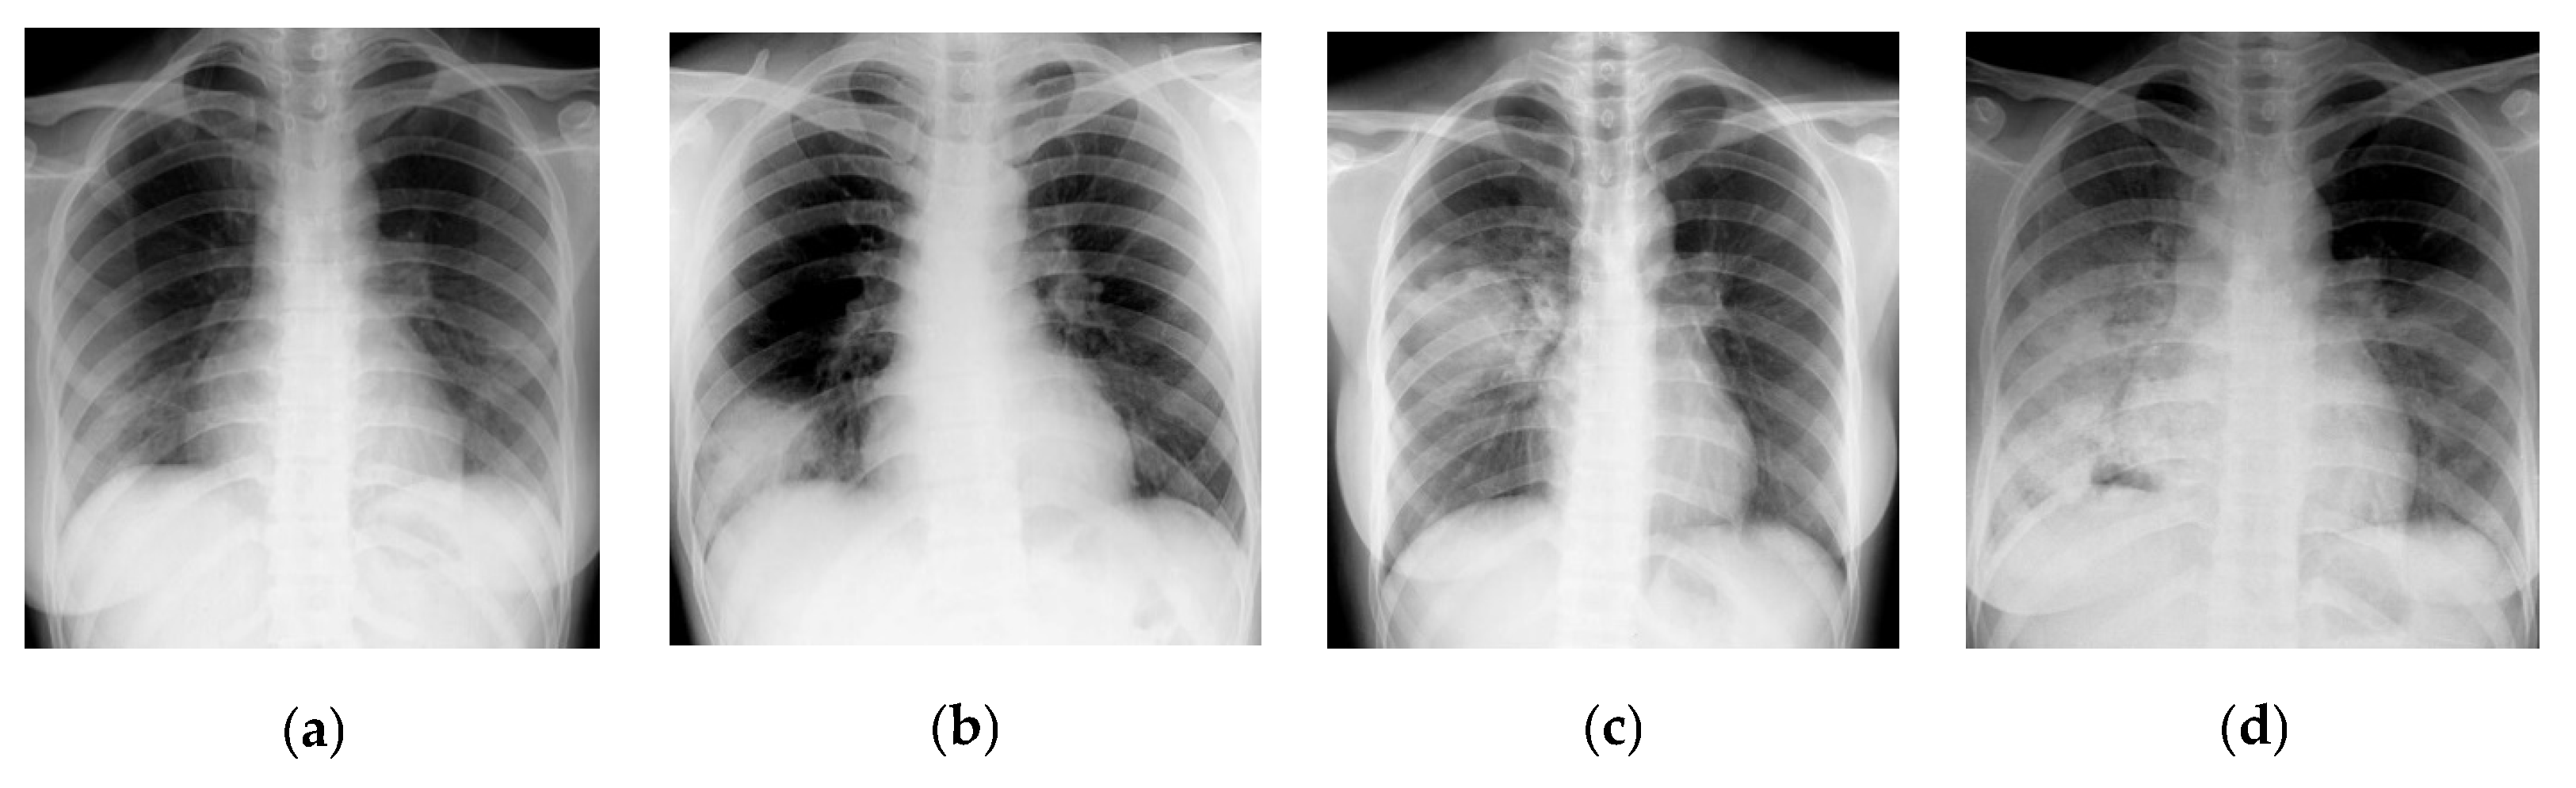

3.2. Texture Quantification of the Time-Series CT Chest Images

Funding